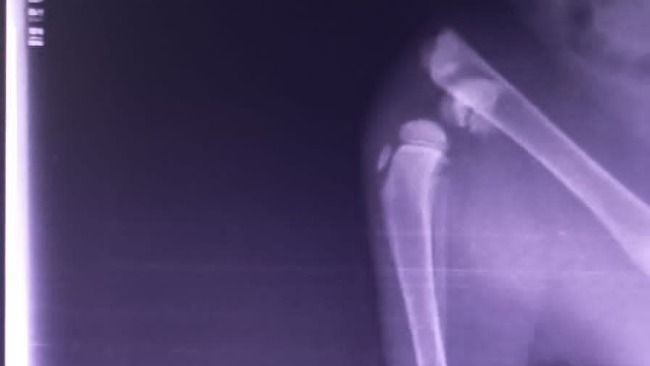

Ma ogromnego krwiaka na lewej tylnej łapce, a RTG wykazało połamanie nasady dalszej kości udowej. To młody kotek, który szybko rośnie. Żeby nie być kaleką, musi przejść pilny zabieg chirurgiczny naprawy łapki!